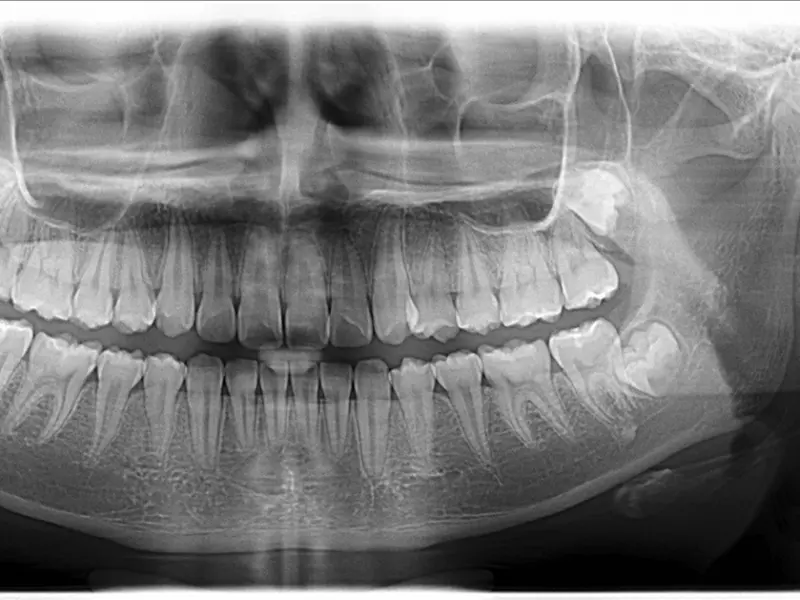

34-letni pacjent zgłosił się do gabinetu dentystycznego z prośbą o wymianę wypełnienia kompozytowego w zębie 36 (lewym dolnym pierwszym zębie trzonowym) (zdj. 1). Ząb ten został przeleczony endodontycznie. Stwierdzono nieprawidłowo ukształtowane wypełnienie kompozytowe wykonane techniką bezpośrednią, szczególnie w okolicy odbudowy guzka językowego dystalnego oraz krawędzi dystalnej. Prowadziło to do częstego zatrzymywania jedzenia wraz z tego negatywnymi skutkami. W porozumieniu z pacjentem i po omówieniu możliwych alternatywnych metod odbudowy oraz kosztów leczenia zdecydowano się na odbudowę bezpośrednią z nanohybrydowego materiału ormocerowego Admira Fusion x-tra (VOCO).